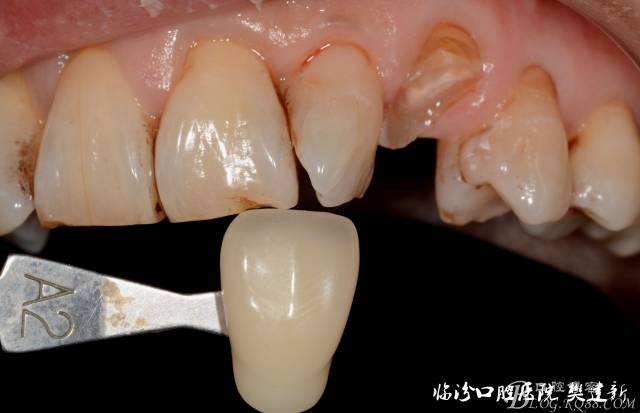

圖1 23口內(nèi)修復(fù)前情況:殘根位于齦上3MM,牙周無紅腫.

圖4 修復(fù)前選色: